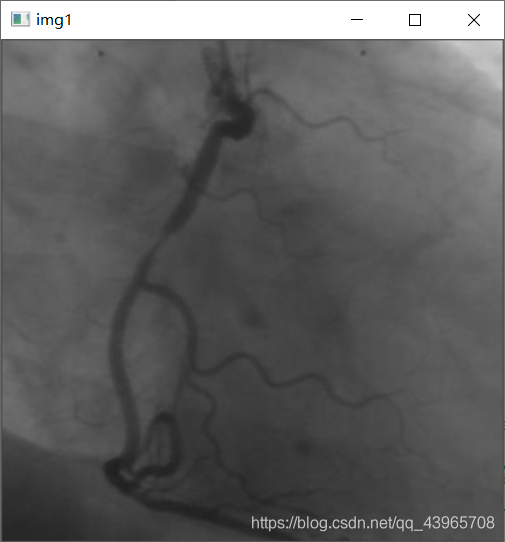

img = cv2.imread(r"C:\Users\pc\Desktop\vas0.png",0)

cv2.imshow("img1",img)

運行結(jié)果